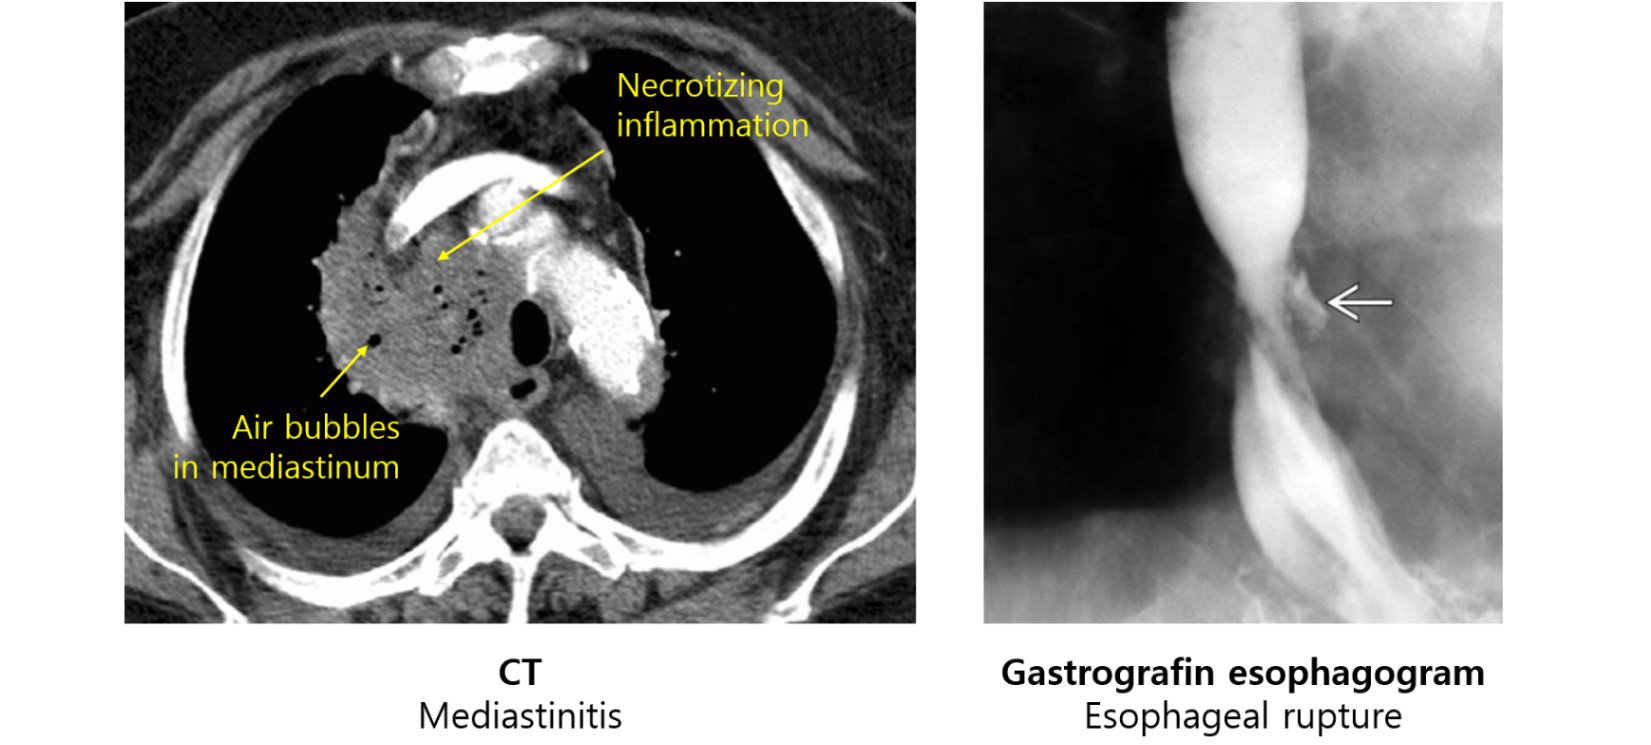

① 식도 파열 → 식도의 공기 및 음식물, 미생물 등이 흉곽(종격동)으로 들어감

종격동기종(pneumomediastinum), 피하기종(subcutaneous emphysema), 종격동염(mediastinitis) 유발

(1) CXR, CT: 종격동기종, 종격동염을 평가

(2) 식도조영술(esophagogram): Gastrografin, barium 등 복용 후 X-ray 촬영